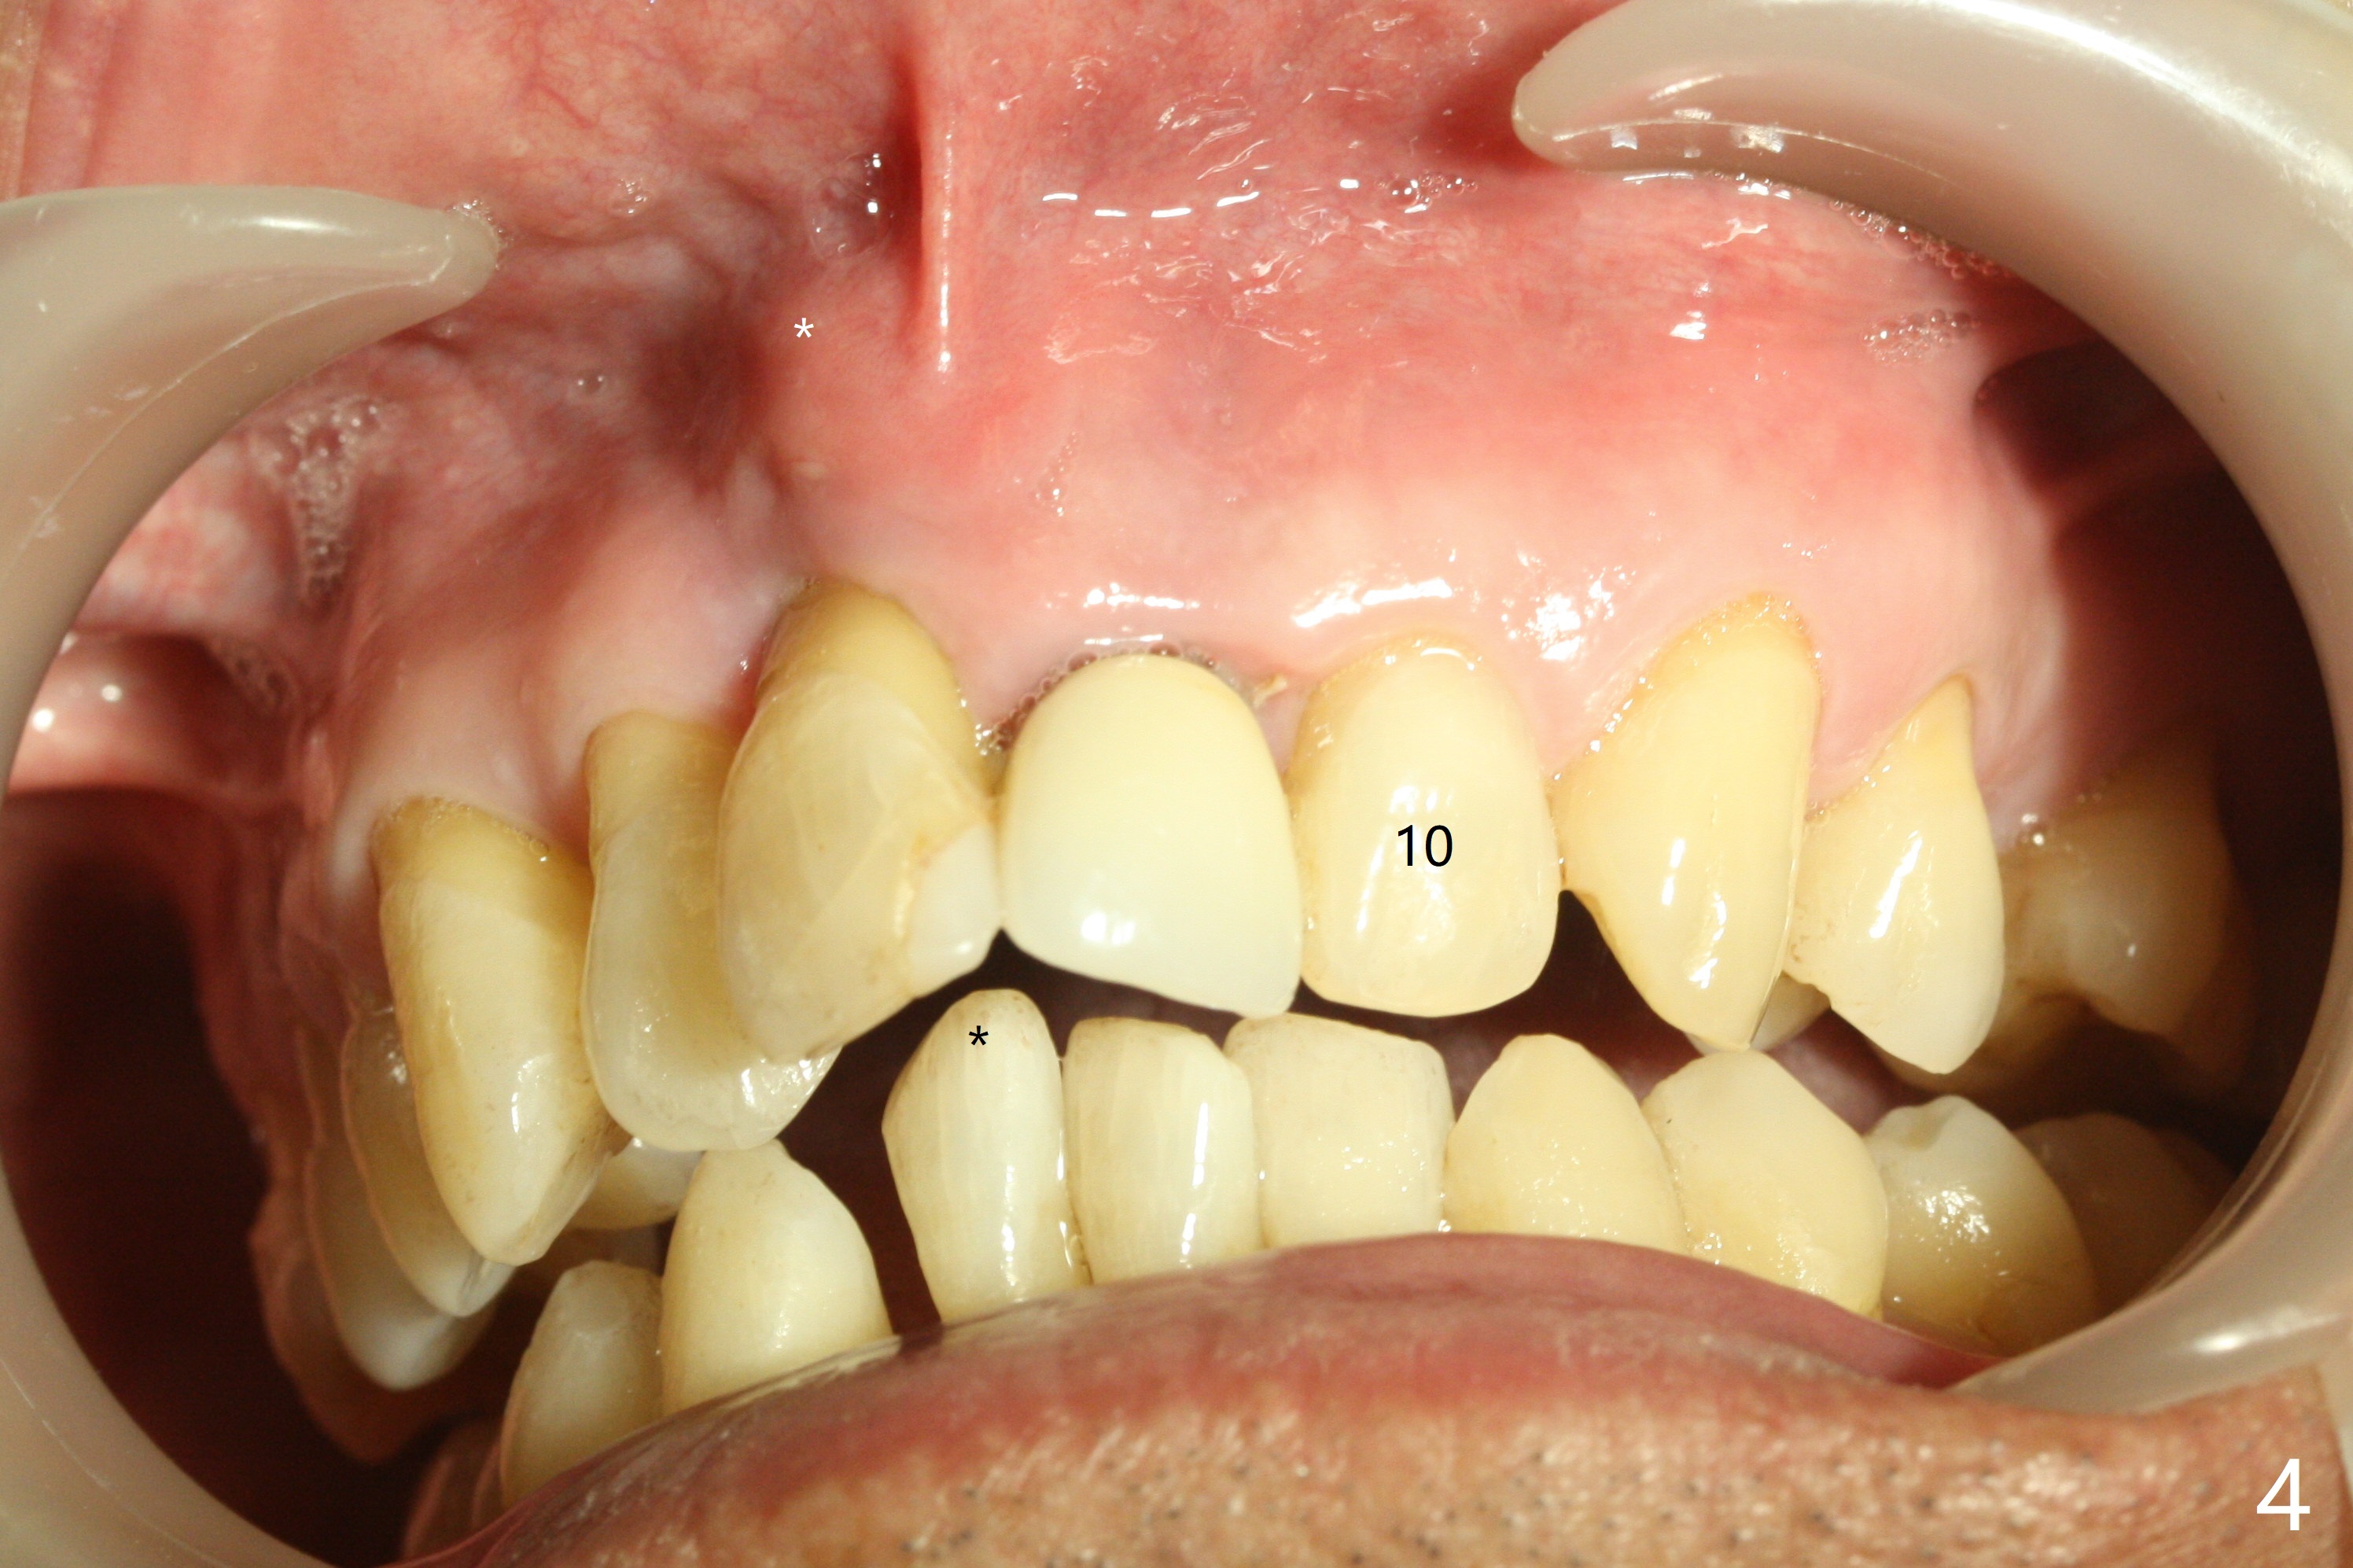

A 59-year-old man requests treatment for buccally displaced upper central incisors (Fig.1,2). It appears that the buccal plate is lost, but the bone height will allow placement of 3.5x13 mm implants with guide (Fig.3). Because of severe infection apical to the tooth #8 (Fig.4,5 *) and truncation of the incisal edges of the upper central incisors during CBCT taking (Fig.6,7 *), guided surgery may not be appropriate. The mesial surfaces of the teeth #7 and 10 and the incisal edges of the lower incisors (*) will be trimmed for immediate provisional. Immediate implants will be placed in the palatal crest of #8 (Fig.6 <) and close to the palatal crest of #9 (Fig.7). Angled abutments are expected (4.5x15 degree, A or B (4 mm cuff). PRF is to be preparedx2 (one for membrane; the other for sticky bone). Take Alginate impression when the patient returns for surgical stent.